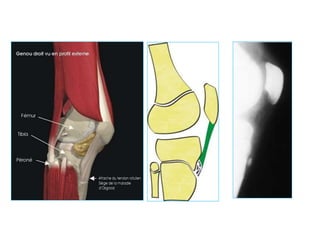

Technique Clocheville

(C.Bonnard)